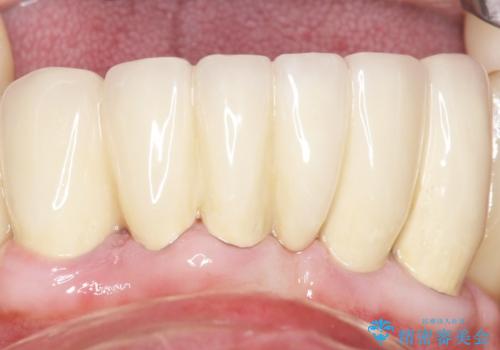

再生療法と骨外科処置により、歯周ポケットは全周2mm以下に改善されました。

保存が難しいと思われた歯を残すことができ、患者様にご満足頂けました。

補綴前に部分矯正を行うことで、歯の神経も保存することができました。

歯周病治療と連結補綴により歯の動揺がなくなり、「なんでも食べられます!」と喜んで下さいました。

生活歯(神経が生きている歯)のため形成量(歯を削合できる量)に限界がありましたが、熟練の技工士さんの素晴らしい技術により補綴を行うことができました。

クラウンの種類:メタルボンドクラウン エコノミー